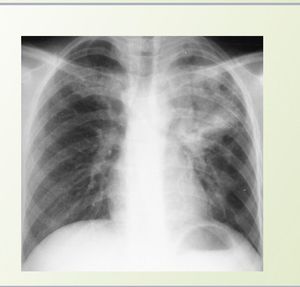

Diagnosis???

Pneumonia

Infection in left lung

No,it is TB